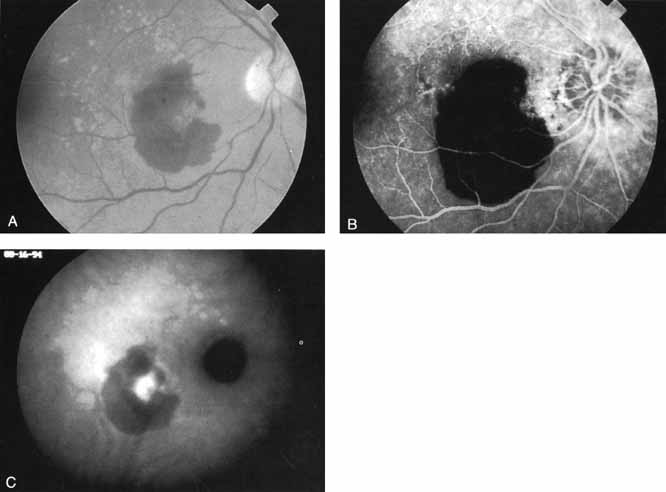

In acute multifocal posterior placoid pigment epitheliopathy, discrete hypofluorescent geographic areas are present both in the posterior pole and extending into the mid-periphery on ICG angiography65,66 (Fig. 16). These hypofluorescent areas are more extensive than noted on either clinical or fluorescein angiographic examination. They are noted in the early phases of the ICG study and persist late, suggesting that ischemic changes in the choroidal circulation occur in this disease. The hypofluorescence remains even once lesions have healed.

Fig. 16 A. Clinical photograph of a patient with acute multifocal placoid pigment epitheliopathy (AMPPE). There is extensive involvement of the central macula by the inflammatory lesions. B. Late-phase indocyanine green angiogram demonstrating extensive confluent but irregular areas of marked hypofluorescence. The hypofluorescence in AMPPE is believed to represent a perfusion abnormality within the choroidal circulation.

Harada disease, an inflammatory condition often affecting both eyes in young patients, is typified on fluorescein angiography by multiple focal areas of hypofluorescence early in the study, followed by late confluent leakage in the later phases (Fig. 17A, 17B, and 17C). With ICG angiography, multiple focal hypofluorescent spots are seen in the early phases, many more than were noted on the fluorescein study64,68 (Fig. 17D). The process extends further than the clinically or angiographically involved areas. The spots vary in size and density but appear to be well circumscribed. In the later phases of the ICG study, there is generalized hypofluorescence, with masking of the background choroidal fluorescence by the neurosensory detachment (Fig. 17E). This masking effect covers a large area, with inferior round margins confirming the gravitating nature of the neurosensory elevation. In addition, focal hyperfluorescent spots can be seen, possibly representing sites of active chorioretinal leakage or inflammation. In one patient, steroid therapy resulted in a marked resolution of clinical findings within 1 week.68 Repeat ICG angiography revealed a marked resolution of the hypofluorescent lesions as well as the hyperfluorescent spots. New areas of hypofluorescence did appear, the significance of which remains undetermined (Fig. 17E).

Fig. 17 Clinical photograph of a patient with Harada disease demonstrating multiple serous elevations of the retinal pigment epithelium with an overlying shallow neurosensory detachment. B. Early-phase fluorescein angiogram demonstrating hypofluorescent spots at the site of localized inflammation. C. Late-phase fluorescein study demonstrating hyperfluorescence in a confluent nature in the central macula. D. Early-phase indocyanine green (ICG) study demonstrating hypofluorescent spots in the central macular region. Note that the lesions are more numerous and more widely distributed than noted on clinical or fluorescein angiographic examination. E. Late-phase ICG study demonstrating extensive areas of confluent hypofluorescence. Note the curvilinear and gravitating nature of these hypofluorescent lesions, which are believed to represent blocked fluorescence from the shallow neurosensory detachment. Focal hyperfluorescent spots are noted within this region, which may represent areas of more active inflammation.